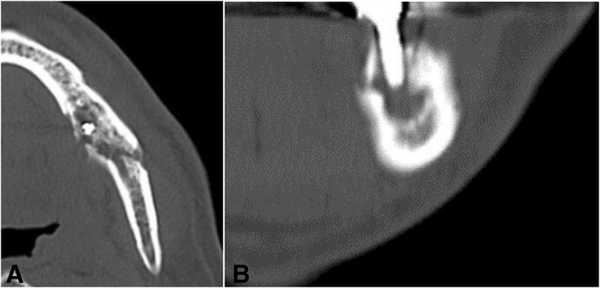

На ортопантомограмме контурировалась слабо демаркационная зона деструкции костной ткани в области имплантатов на месте 35 и 36 зубов, при этом поражение достигало нижнего края челюсти, что в результате спровоцировало возникновение патологического перелома. Вокруг имплантатов с правой стороны челюсти никаких патологических поражений отмечено не было (фото 2). С помощью КТ-сканирования удалось подтвердить деструкцию нижней челюсти слева и наличие линии перелома через всю толщу костной ткани (фото 3).

Фото 3. КТ-изображения нижней челюсти с левой стороны: а) аксиальный срез в области левого первого моляра; b) корональный срез в области левого первого моляра.